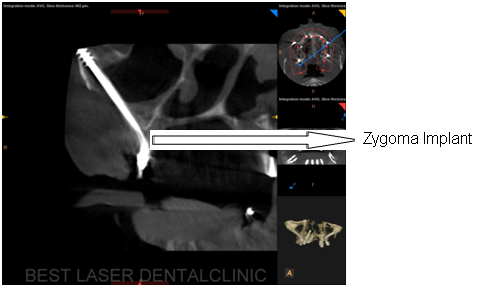

CASE REPORT OF PATIENT WITH ECTODERMAL DYSPLASIA TREATED BY

ZYGOMA IMPLANTS

Before and After 3D -CBCT Images

What is guided zygoma implant?

• In this technique, zygoma implants are placed with the guidance of specially made surgical guides, this help the surgeon to accurately place zygoma implants.